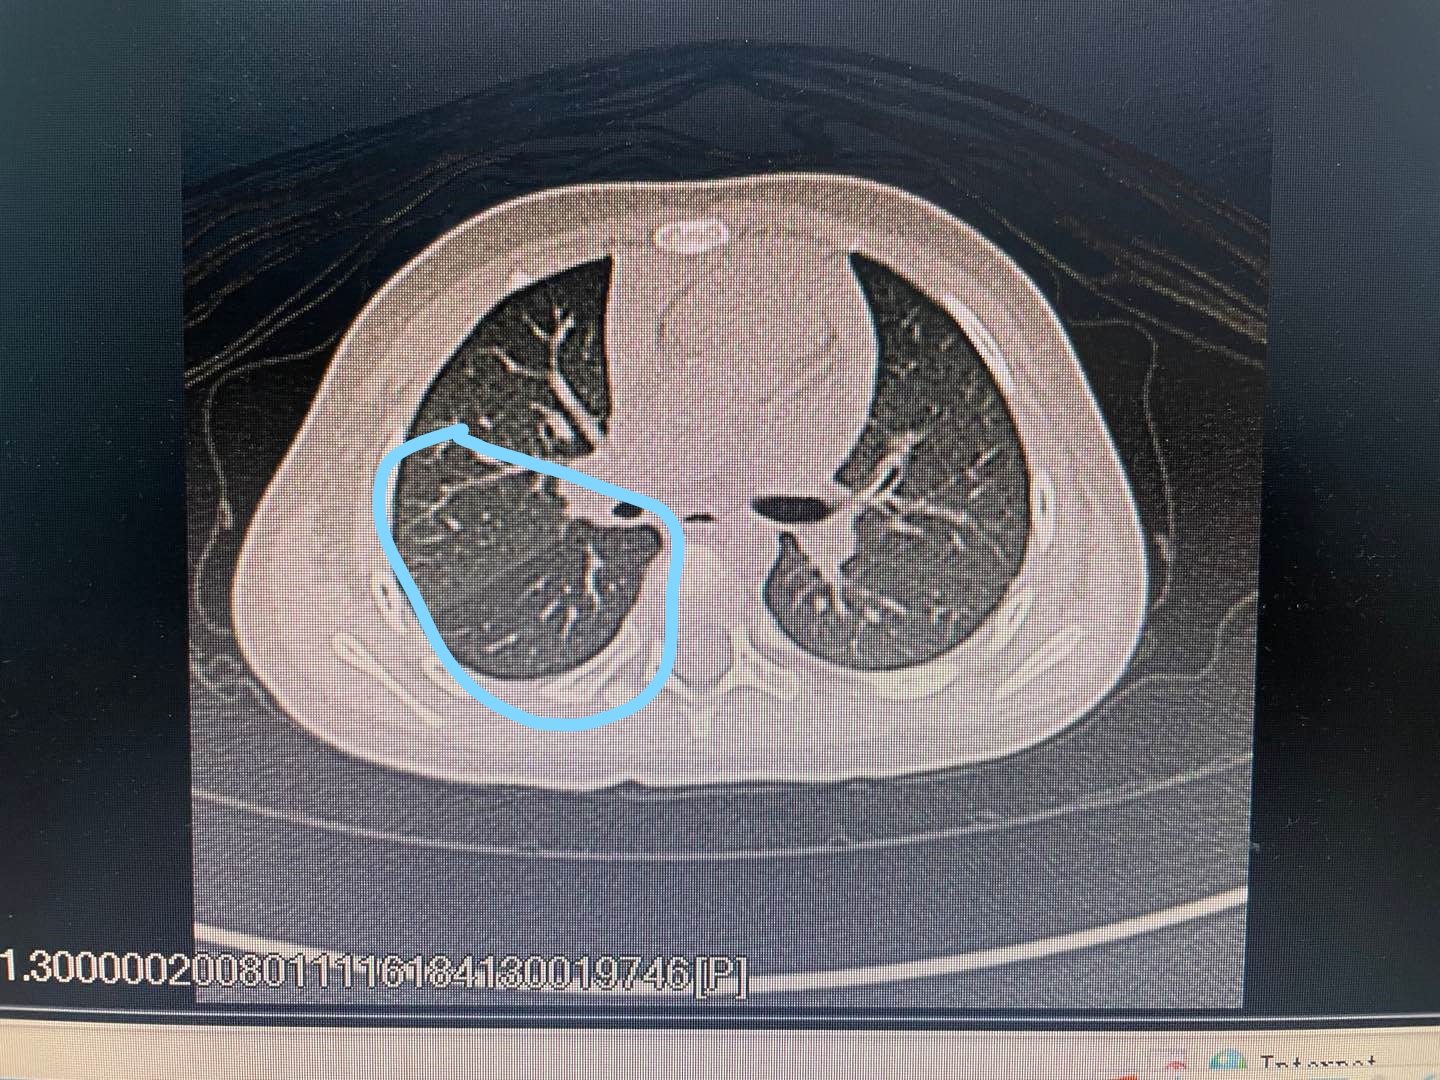

马上急查了胸部CT+气道三维重建,如下图所示:

圈圈里面,右肺下叶有透光度增强,右主支气管内可以见到条形稍高密度影(面条)

图片上可以看出,圈圈里面的,右侧肺部下叶明显一个透光度增强,部分的支气管有闭塞的情况出现